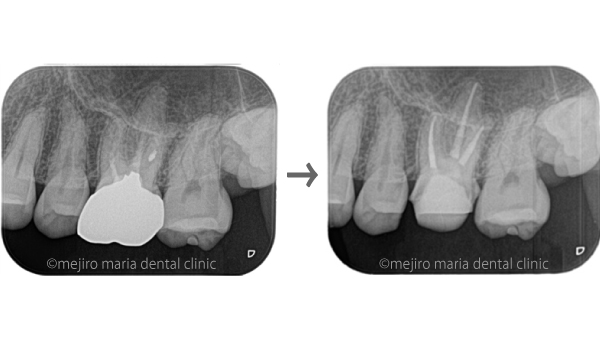

目白マリア歯科の症例

当院では、精密根管治療だけでなく様々な治療の症例を紹介しています。

各分野に特化した歯科医師による、専門的な歯科医療を行っています。